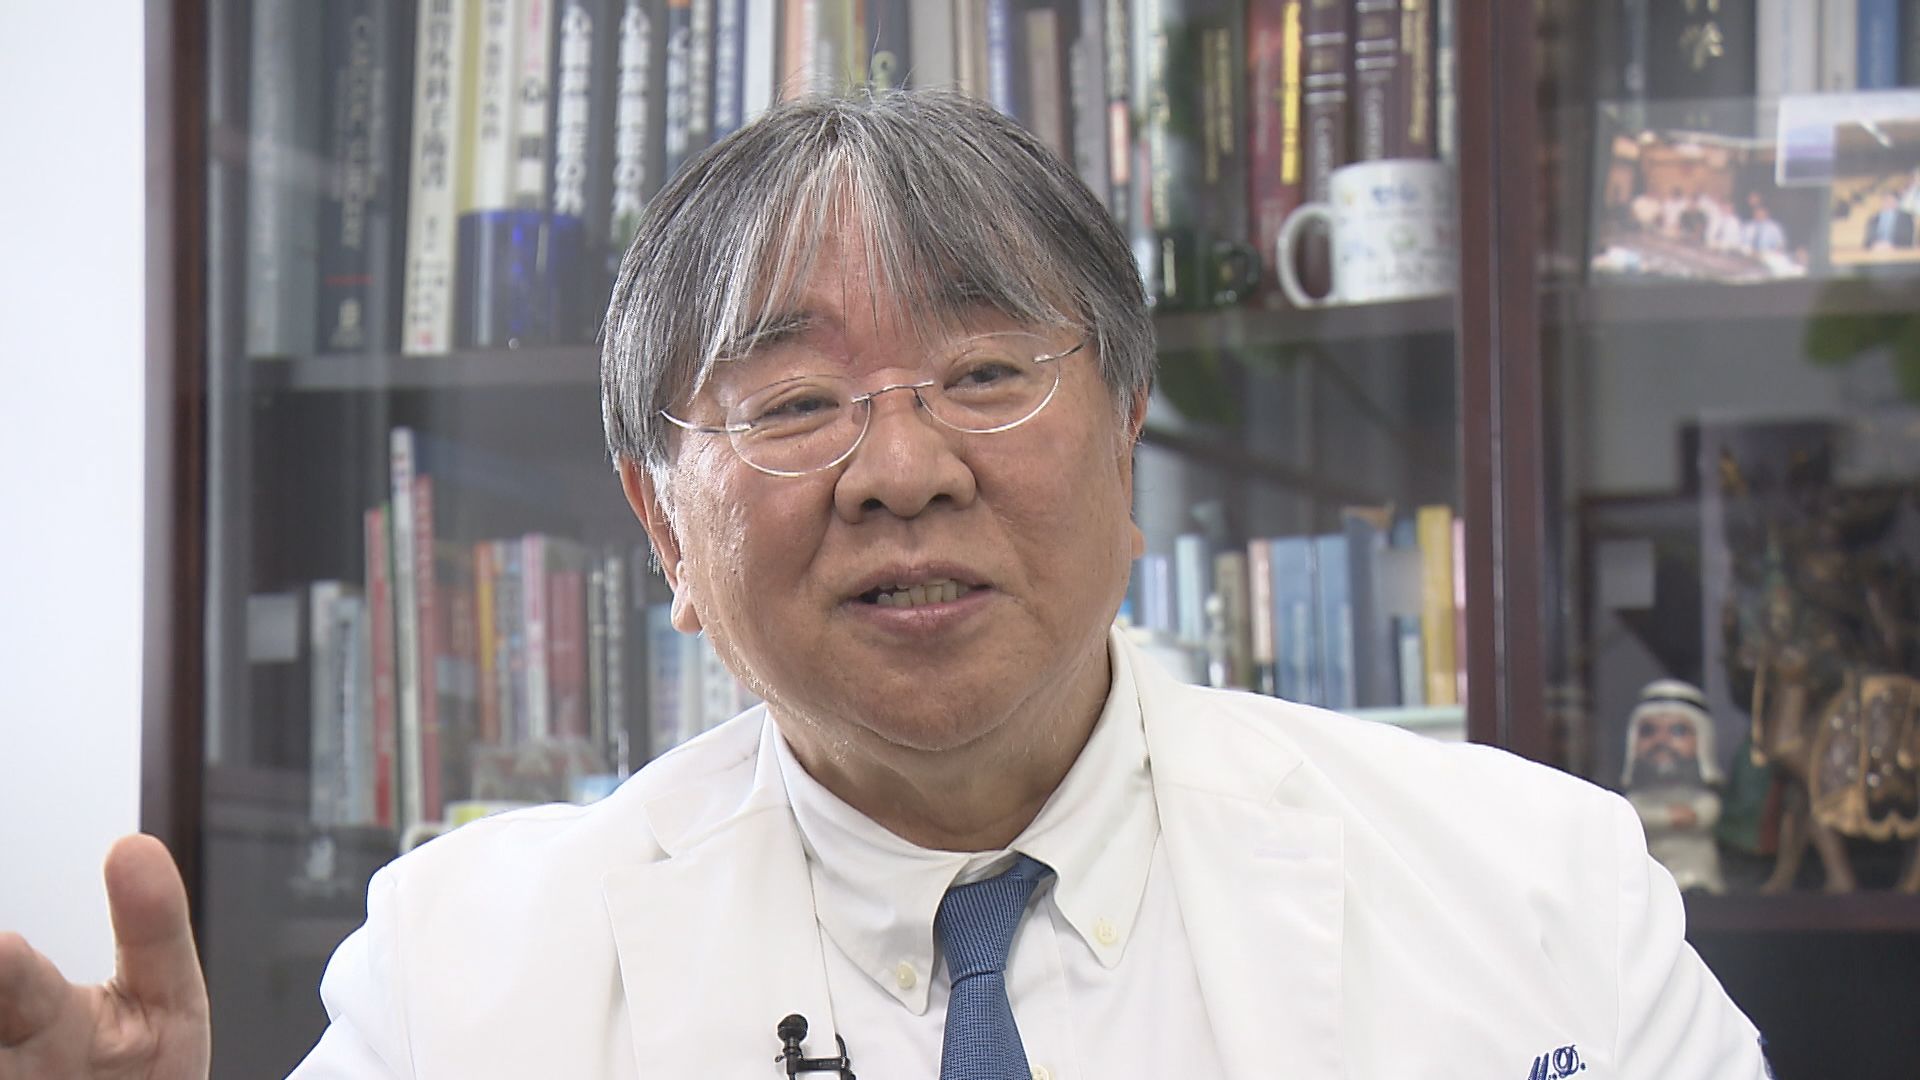

iPS心臓モデルを手がけるのは、大阪大学発のベンチャー企業「クオリプス」。

最高技術責任者を務めるのが大阪大学の澤芳樹特任教授(70)だ。

心臓外科医の澤教授だが、幼いころは、医師を目指していなかったという。

【大阪大学・澤芳樹特任教授】「私は機械や乗り物が好きだったので、機械工学とか、そっちの方に実は進みたかったんですよ」

しかし、高校2年の夏、駆け出しの医師だった「従兄」の死が、澤教授の人生を変えた。

【大阪大学・澤芳樹特任教授】「従兄は私より10歳上でした。大阪大学医学部を卒業して、研修医を終わり、ちょうど若手バリバリの医者になったころ、5月にお会いしたんです。『君は頑張って医者になってくれよ』と励まされて。そのときはもうポカーンと僕は口が開いていて『何を僕に期待してんのかな』とか思っていたら、その3ヶ月後に交通事故で亡くなったんですよ」

【大阪大学・澤芳樹特任教授】「暑い8月の最初のころかな。お兄さんの家に行って、そのご遺体に接してですね『あの時、あれだけ僕を励ましてくれた人が、何でこんな簡単に死ぬの』と、しかも、27歳で亡くなったんですね」

「何なんだろうと『人ってどうしてそんな簡単に死ぬのだろう』と。その時に、本当に耐えられない気持ちの中で、そういえば、従兄は『君に医者になってほしい』と言ってくれていたなというのが、やっぱ大きなきっかけですね。それぐらいから、高校の勉強の本気さが変わりました」

■「白い巨塔」のモデル 大阪大学医学部第一学科に入局

従兄の死がきっかけで、大好きだったバスケットボールを辞めて、勉強一本、医師を目指した澤教授。

見事、従兄と同じ大阪大学医学部に現役で合格した。

好きな映画は「白い巨塔」。

入局したのは、映画のモデルとなった大阪大学医学部第一外科だった。

【大阪大学・澤芳樹特任教授】「特に第一外科の中でも、命に一番直結する心臓外科を選んで、まっしぐらでした」

【大阪大学・澤芳樹特任教授】「医者になった時に、心臓病の人を一人でも救いたいと、自分は努力したつもりです。その中で治せない患者さんがたくさんいらっしゃって、医師として苦しくつらい思いをしました。新たな方法を用いて助けることができたらという思いで、何十年も研究を続けてきたわけです」

「我々の治療が、ほんとに実現したら、最終的には『心臓病で死なない世界』ができるのではないかと私は思っています。それをどう実現していくかですね、これからまだまだ乗り越えなければならないステップがあるわけです。新たな若い人たちが、この研究の道に入ってもらって、一人でも多くの命が助かる道を、一緒に進めてほしいと思っています」

「『万博で見た時、あんなもんだったけど、人に使える、臨床に使えるようになったね』と、そういうところまで進化するように、若い人に刺激を与えたいというのが、僕が一番やりたいことです。iPS心臓モデルを見た人の中から『ゲームチェンジャー』が出てきてほしいんです」

澤教授は、50年後にはiPS心臓の移植が当たり前になる時代がやってくるのではないかと期待している。